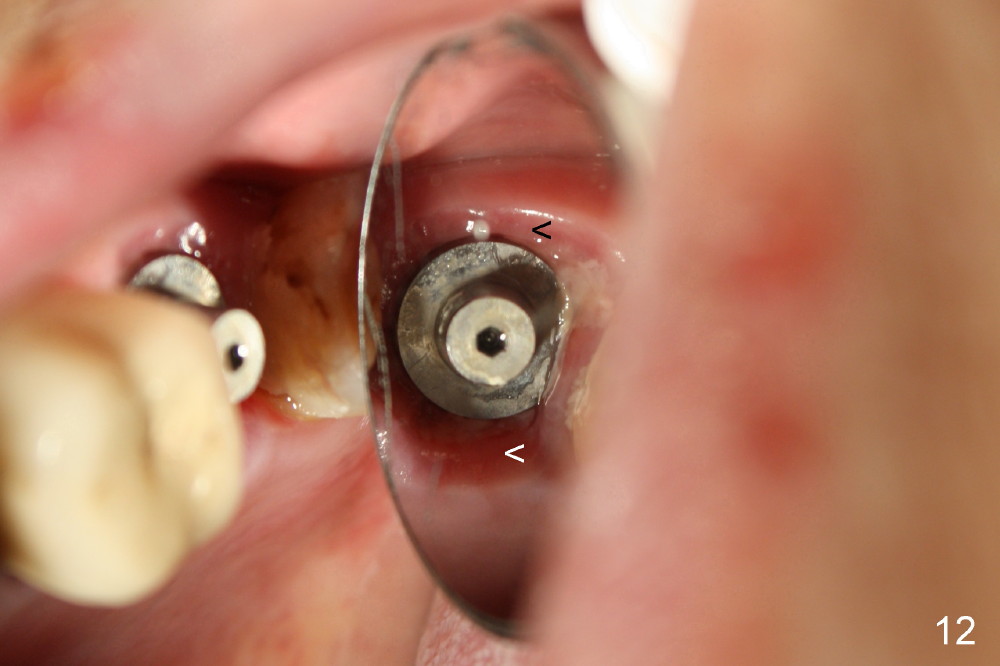

A 66-year-old lady requests restoring a broken tooth (Fig.1). Osteotomy is initiated in a thin septum (Fig.2 (occlusal mirror view) S) by sectioning, drilling and tapping (Fig.3 T). When 7x17 mm tap is removed, the osteotomy is found to form basically in the middle of socket (Fig.4 O). The apical portion of three sockets (Fig.5: MB, P and DB (not labeled) is packed with mixture of autogenous bone and allograft. When a 7x14 mm implant is placed, there are buccal and lingual gaps (Fig.6 *). The latter are bone grafted again (Fig.8 *) and require a coverage. After placement of a 4x3 mm abutment (Fig.7,8 A), an immediate provisional is fabricated (Fig.9 tissue surface view) to cover the remaining sockets (Fig.10 (occlusal mirror view), 11 (buccal view)). The provisional is infra-occlusal, i.e., load-free (Fig.11). The buccal and lingual aspects of the socket are covered by fresh epithelium 8 days postop (Fig.12 <). The implant appears to have osteointegrated 4 months postop (Fig.13). The tooth #16 appears to have shifted mesially. It is difficult to prepare for #15 crown. Luckily the patient agrees to have it extracted because of persistent sensitivity after MO composite. The definitive crown at the site of #15 is cemented 6 months postop (Fig.14).